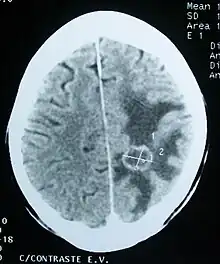

Imaging

Medical imaging plays a central role in the diagnosis of brain tumors. Early imaging methods – invasive and sometimes dangerous – such as pneumoencephalography and cerebral angiography have been abandoned in favor of non-invasive, high-resolution techniques, especially magnetic resonance imaging (MRI) and computed tomography (CT) scans, though MRI is typically the reference standard used.[37] Neoplasms will often show as differently colored masses (also referred to as processes) in CT or MRI results.

- Benign brain tumors often show up as hypodense (darker than brain tissue) mass lesions on CT scans. On MRI, they appear either hypodense or isointense (same intensity as brain tissue) on T1-weighted scans, or hyperintense (brighter than brain tissue) on T2-weighted MRI, although the appearance is variable.

- Contrast agent uptake, sometimes in characteristic patterns, can be demonstrated on either CT or MRI scans in most malignant primary and metastatic brain tumors.

- Pressure areas where the brain tissue has been compressed by a tumor also appear hyperintense on T2-weighted scans and might indicate the presence a diffuse neoplasm due to an unclear outline. Swelling around the tumor known as peritumoral edema can also show a similar result.

This is because these tumors disrupt the normal functioning of the BBB and lead to an increase in its permeability. More recently, advancements have been made to increase the utility of MRI in providing physiological data that can help to inform diagnosis and prognosis. Perfusion Weighted Imaging (PWI) and Diffusion Weighted Imaging (DWI) are two MRI techniques that reviews have been shown to be useful in classifying tumors by grade, which was not previously viable using only structural imaging.[38] However, these techniques cannot alone diagnose high- versus low-grade gliomas, and thus the definitive diagnosis of brain tumor should only be confirmed by histological examination of tumor tissue samples obtained either by means of brain biopsy or open surgery. The histological examination is essential for determining the appropriate treatment and the correct prognosis. This examination, performed by a pathologist, typically has three stages: interoperative examination of fresh tissue, preliminary microscopic examination of prepared tissues, and follow-up examination of prepared tissues after immunohistochemical staining or genetic analysis.